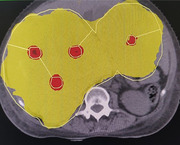

Purpose: Lattice radiotherapy can potentially deliver high doses to the tumor core, while conventional doses to the periphery resulting in improved response rates in large tumors (> 5 cm). We assessed the feasibility of planning lattice radiotherapy and dosimetrically compared it with conventional radiotherapy.

Methods: This retrospective dosimetric study evaluated 10 patients with large tumors (> 5 cm) treated with palliative intent with a dose of 20Gy in five fractions. High-dose lattice points were created at doses of 50Gy in non-hepatic tumors and 35Gy in hepatic tumors. Lattice plans were compared with treatment plans regarding dose coverage and organ-at-risk dosimetry.

Results: Treated sites included soft tissue metastases to the neck, lungs, abdomen, pelvis, and liver. The mean lesion volume was 1103 cc (352-3173 cc). The maximum tumor size was 16 cm. The target volume coverage was > 95% in all but one case (88% to achieve organ constraints). Dosimetry and organ-at-risk doses were similar in both palliative treatment and simulated lattice plans.

Conclusion: Lattice radiotherapy is feasible in large tumors using volumetric-modulated arc therapy and achieves good coverage while meeting organ constraints. However, a prospective clinical evaluation is required to confirm its efficacy.